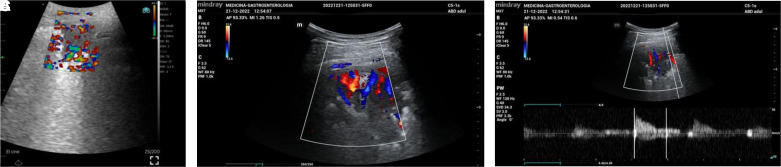

Abstract Image